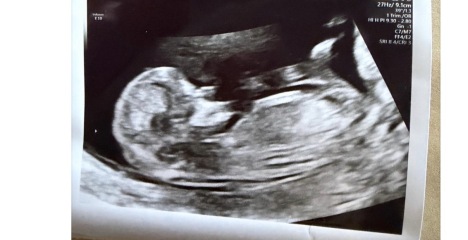

12-week scan, any guesses whether baby is a boy or girl?

12 weeks scan boy or girl any guesses x

I reckon boy x